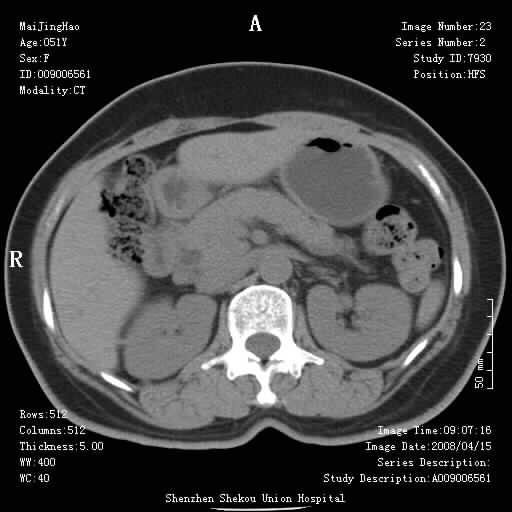

以下是引用余辉在2008-4-26 8:55:00的发言:[br]患者有结石史,此次腹痛4小时,胆总管全程扩张,应有胆总管末端梗阻,此次仍考虑胆结石症,积气不外两种原因,一种是结石下移时肠道内气体逸入,其次为产气菌感染。(倒数第三幅图像于扩张之胆总管末端似可见稍高密度影,考虑为结石影)

以下是引用听蝉观竹在2008-4-26 11:41:00的发言:[br]胆道手术分两种情况:[br]1、如果仅仅做胆囊切除手术,肝内胆管不会积气,只会出现胆总管代偿扩张,因为奥迪氏括约肌依然功能正常胆道与外界并不相通;[br][br]2、胆囊切除+胆总管空肠吻合手术(即roux-y式),则肝内胆管会出现积气,只是因为胆管与小肠相通,气体来源于小肠。这是临床十分常见的手术。[br][br]这个病例应该是胆囊切除+胆总管空肠吻合手术,是正常手术后表现,并不是胆道感染的表现。